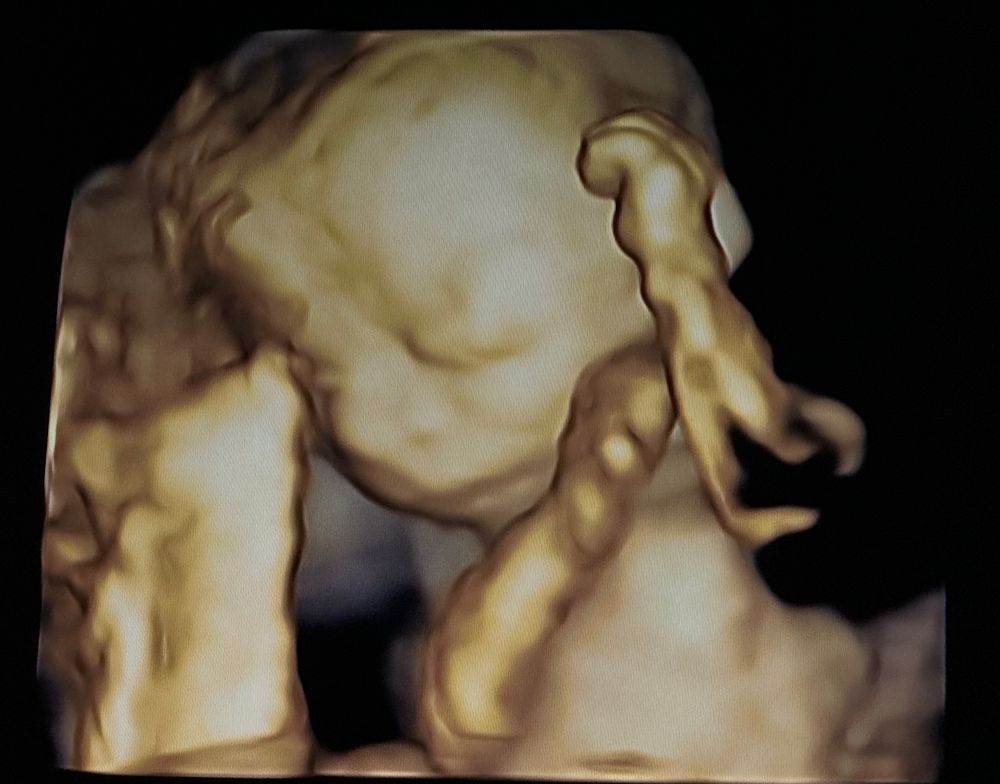

жду мальчика, 26 неделя

Второй скрининг пройден 🙃

Мы прошли второй скрининг, у нас всё прекрасно ☺️

Прошли на прошлой неделе, на сроке 20.5н, вес малыша был около 365гр, по всем показателям всё хорошо.

На 3д уже прямо человек виден! Растите здоровыми и дальше 😊

Lena, да, на некоторых снимках еще лучше пойман был))